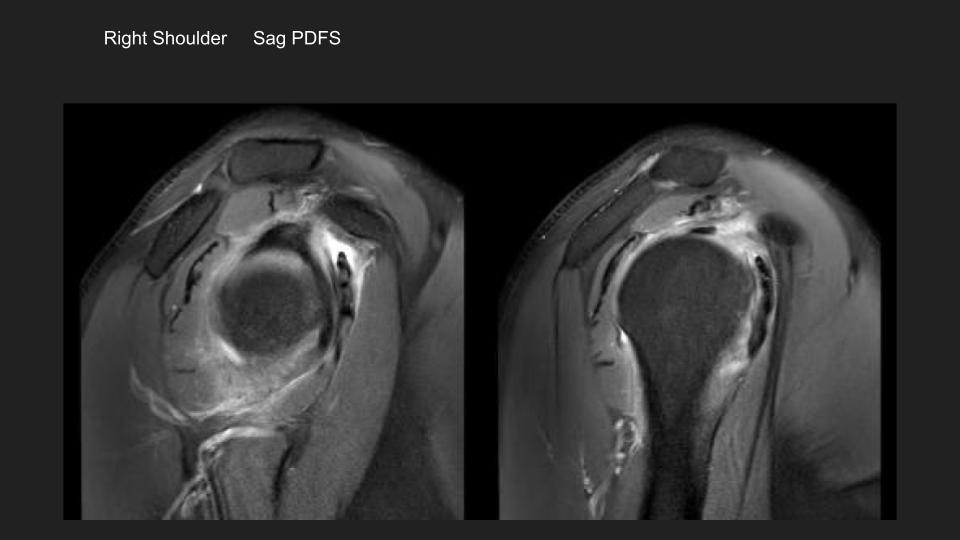

5.jpeg